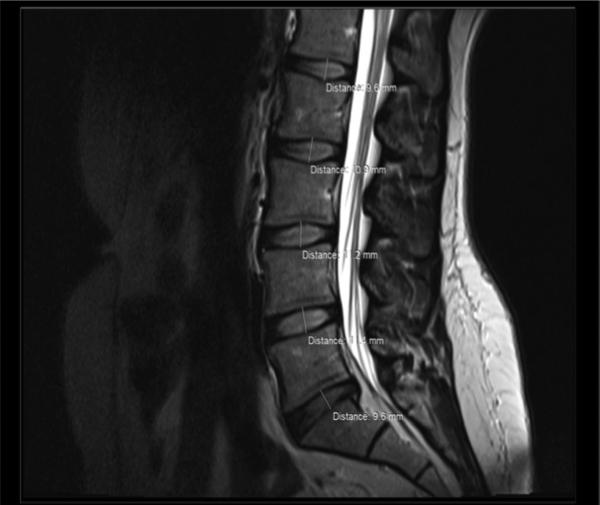

椎间盘是上下两节脊椎骨中间的软骨盘,由上下两个软骨板、外层环状纤维环和中间的髓核组成。

所以,当脊柱不稳定时,椎间盘是最容易受伤的。间盘的纤维环一旦破了,就是椎间盘突出了。

如果突出刚好压迫了神经根,引起了神经根症状,才是腰椎间盘突出症。